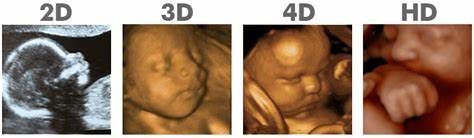

- What is the difference in 2D/3D/4D/HD?